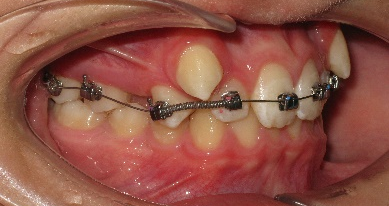

В полости рта: смыкание первых моляров по дистальному типу. Сужение зубных рядов в боковых отделах. 13 и 23 - вестибулярное и супраположение с дефицитом места в зубном ряду на величину ширины коронки клыка. Глубокая резцовая окклюзия.(рис.2.)

Рис.2.Смыкание зубных рядов пациента А. до лечения и окклюзионный вид.

В последующем, после дистализации моляров на верхней челюсти, аппарат снят и на втором этапе ортодонтического лечения фиксирована брекет-система пассивного самолигирования NexStep Pro с пазом 0.22 (стандарт). Уникальная конструкция замка-слайда обеспечивает повышенный контроль торка и ротации, а прецизионность паза брекета дает полную реализацию программы, заложенную в брекетах данной системы SLS. (рис.6 )